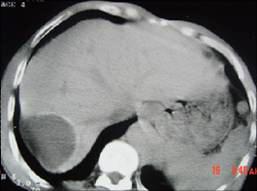

问题 女,62岁,右上腹隐痛,曾在新疆生活30余年,有犬、羊密切接触史,CT平扫如图,最可能的诊断是 ( )

选项 A、肝血管瘤 B、肝包虫病 C、肝癌 D、肝脓肿 E、肝囊肿

答案 B